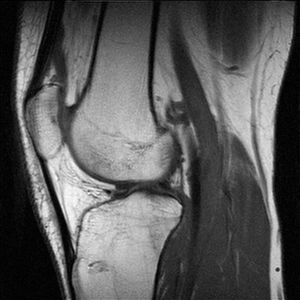

للرنين المغناطيسي أستخدمات تشخيصية متعددة لأنه قادر و بدقة عالية على تصوير الأنسجة الداخلية دون التركيز على العظام مما يساعد على تشخيص الأورام خبيثة أو حميدة التي تنبع من الأنسجة